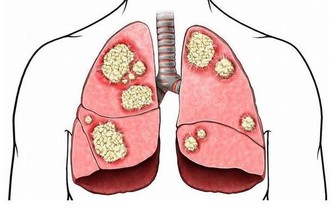

如何幫助肺部排毒?霧霾的存在讓我們越來越重視肺部的健康問題,從而也引伸到了肺部排毒的問題。

該如何養護我們的肺部,幫助肺部排毒,來看看中醫有什麼方法。

中醫認為,「肺為嬌臟」,「溫邪上受,首先犯肺」,肺是最容易受到外來有害物質侵害的臟器。

肺部有毒的表現症狀

肺毒的原因:肺毒也叫氣毒,主要和空氣品質有關,

肺毒的表現:呼吸不暢、胸悶、咳痰。